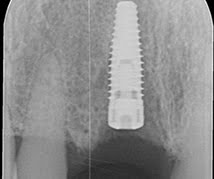

This patient had lost his upper right central incisor and premolar due to historic gum problems. Although a challenging case requiring bone grafting, we achieved a very natural result with dental implants. The patient was delighted.

Before Treatment, Central Incisor Missing

Before Treatment with Lips Retracted

Implant in Optimal Position

Bone Graft Placed

Implant Restored with Natural Looking Crown

After Treatment,

a Great Result